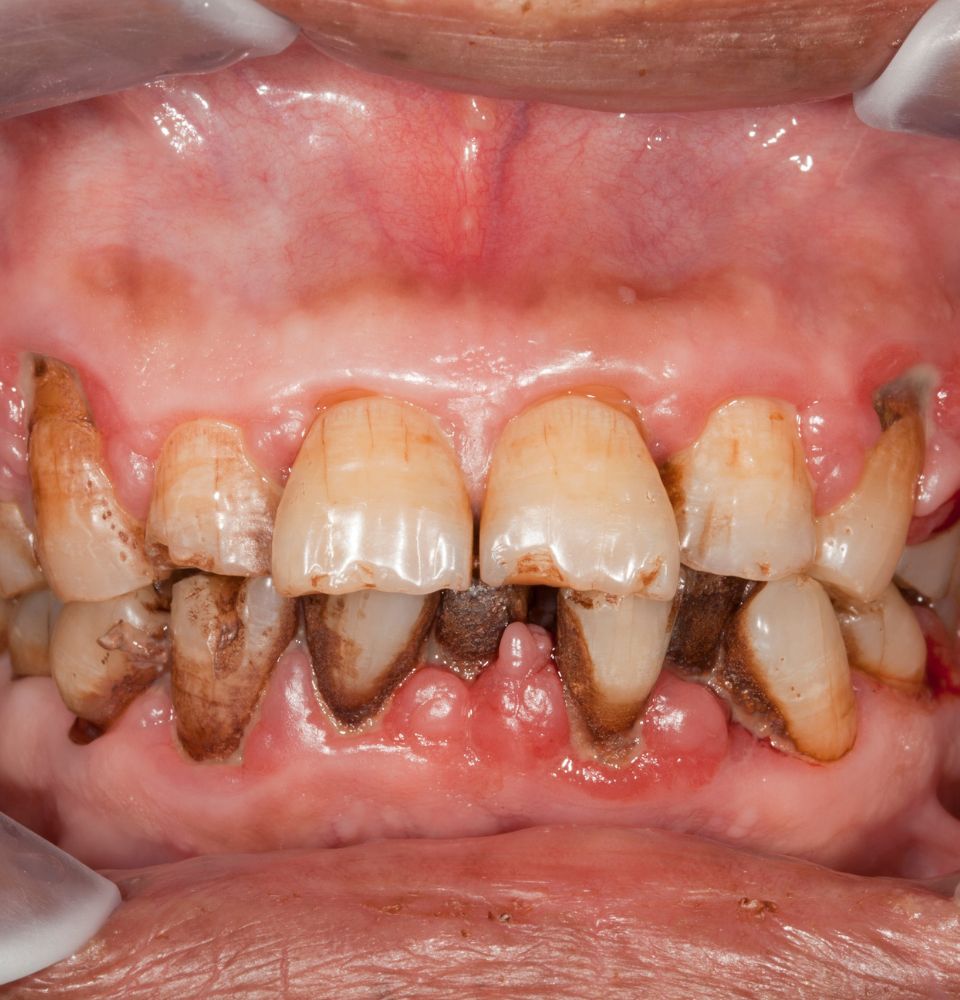

Les plus évidentes sont la mauvaise haleine et la coloration des dents.

Plus sérieusement, le tabagisme a été associé à un risque accru de maladie parodontale, à une perte osseuse accrue dans la mâchoire et au cancer de la bouche.

Les fumeurs ont deux fois plus de risque de maladie des gencives qu’un non-fumeur.

Selon l’Académie de parodontologie, l’usage du tabac est l’un des facteurs de risque les plus importants dans le développement et la progression des maladies des gencives.

Non seulement le tabagisme a été associé à une probabilité accrue de maladie des gencives, mais il a également été constaté qu’il rendait le traitement de la maladie des gencives moins efficace.

La maladie des gencives est la principale cause de perte de dents.